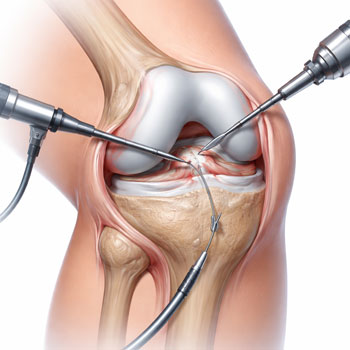

What orthopedic services are available?

We provide advanced orthopedic care including joint pain treatment, fracture management, arthritis care, and minimally invasive procedures with expert specialists at Jayabhrathi Multi Specialty Hospital